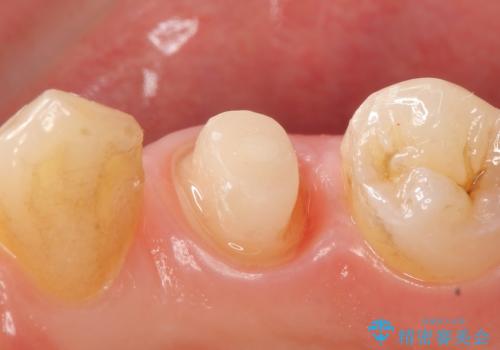

X線上で根尖病変を認めたため再根管治療を行い、症状改善後、オールセラミッククラウンによる補綴を行いました。

- オールセラミッククラウン(st)…¥100,000、仮歯…¥10,000、ファイバーコア…¥20,000費用は治療当時の料金となります

今回用いたオールセラミッククラウンはジルコニアフレームという白い素材の上にセラミックを盛っているため、審美性が非常に高いのが特徴です。

また、ジルコニアは人工ダイヤモンドの材料にも使われているほど高い強度を持っており、そのためオールセラミッククラウンは審美性だけでなく、奥歯やブリッジの補綴も可能とするクラウンです。